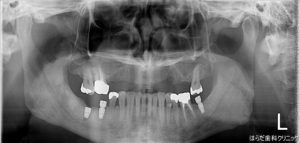

こちらがインプラント体埋入後のレントゲン写真です。

右下(写真では左下)7番にしっかりと埋入されています。

このあと骨に定着するのを待ち、次の段階に進みます。